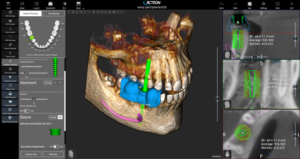

Tomograf X-mind Trium

Tomograf komputerowy będący nowatorskim system do obrazowania cyfrowego. X-Mind Trium wyposażony jest w algorytm akwizycji i rekonstrukcji, zapewniający najwyższej jakości obrazy dla wszystkich projekcji.

Sprzęt ten gwarantuje duże bezpieczeństwo pacjentów, dzięki znacznie ograniczonemu narażeniu badanego na promieniowanie. Innowacyjny algorytm redukuje natężenie prądu (mA) o 50% zmniejszając dawkę pochłoniętą przez pacjenta, nie powodując przy tym utraty jakości obrazu!

Tomograf X-MIND® trium 3D znacznie przyspieszających pracę implantologa. Przestrzenna mapa gęstości kości wokół planowanego implantu pozwala na uzyskanie pełnej informacji i zwiększenie bezpieczeństwa zabiegu.

W TROSCE O NAJMŁODSZYCH

Aby chronić dzieci wprowadzony został dodatkowy ruch czujnika, który pozwala zbliżyć go do głowy i jeszcze bardziej obniżyć dawkę pochłoniętą przez małego pacjenta.